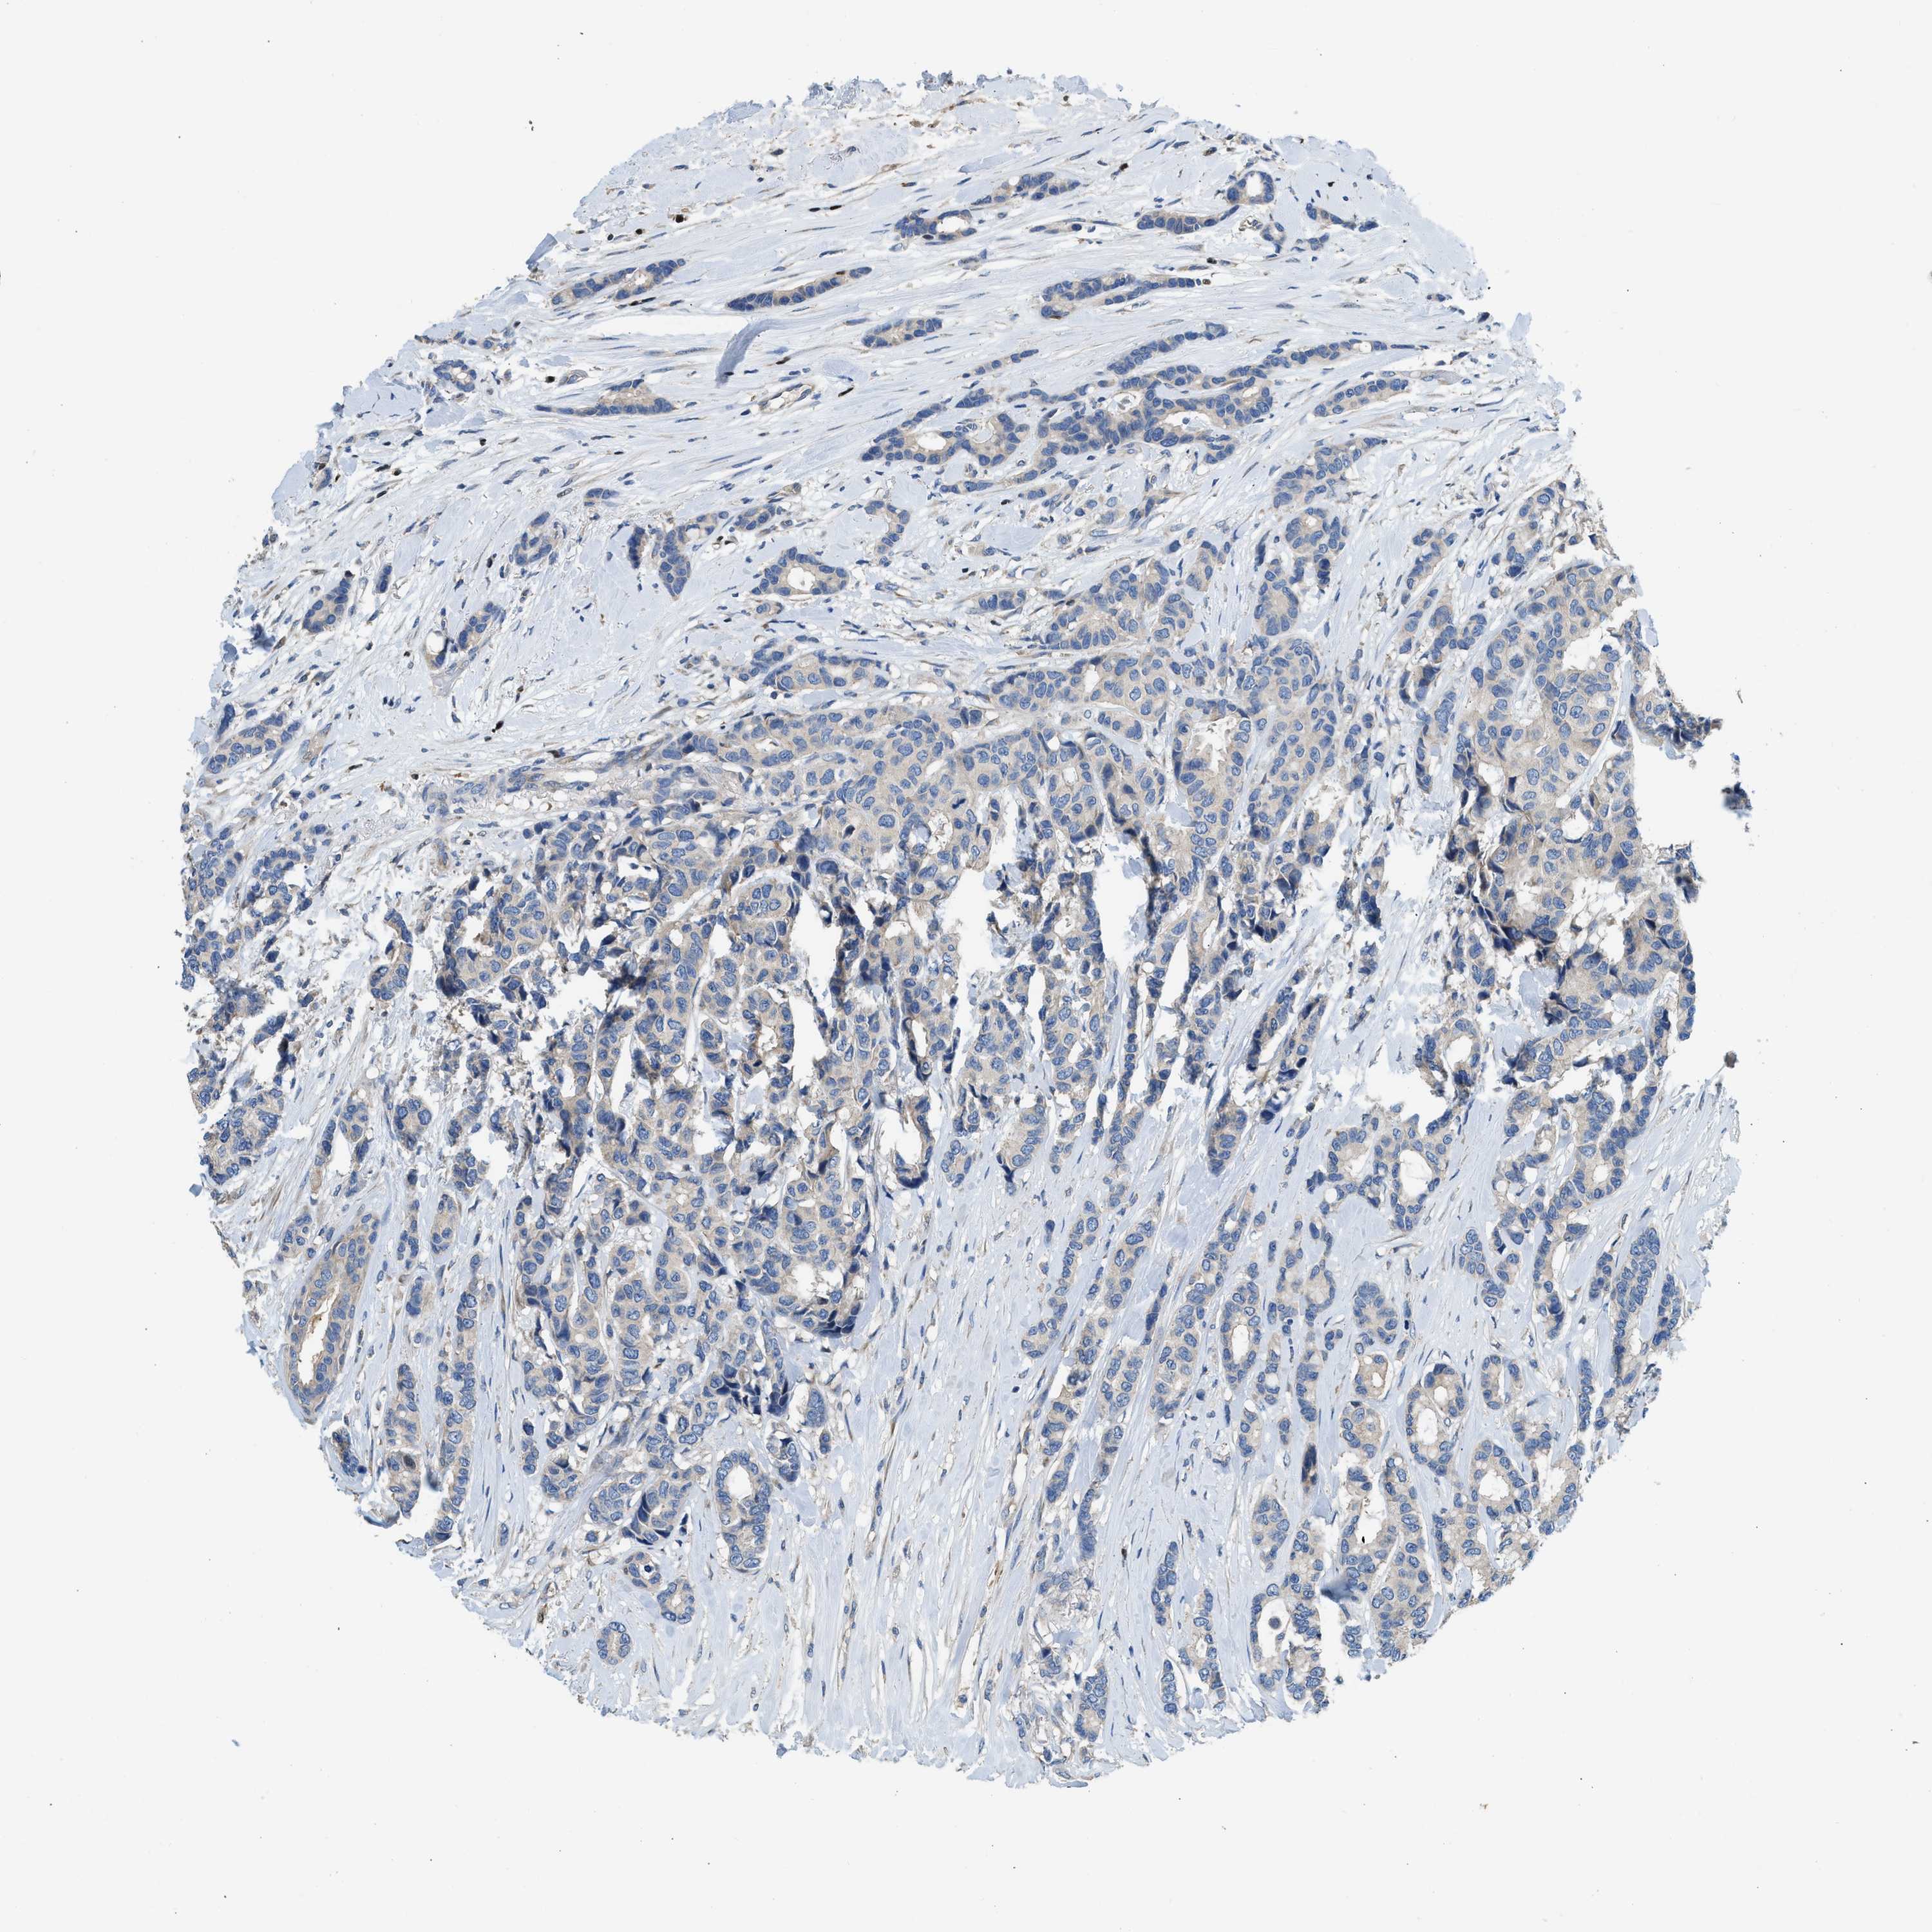

CANCER BREAST CANCER Show tissue menu

BRCA TCGA BRCA VALIDATION PROTEIN EXPRESSION

ANTIBODIES

AND

VALIDATION